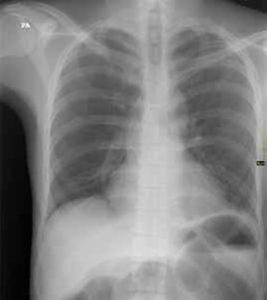

Entre sus exámenes de laboratorio se destacaba una hipopotasemia leve; en el estudio de radiología simple de abdomen, en bipedestación y posición supina, se observó un patrón de ‘pilas de monedas’ (figuras 1, 2, 3).

Figura 3. Radiografía simple de abdomen en bipedestación: distensión de asas de intestino delgado, niveles hidroaéreos y ausencia de gas en el recto.